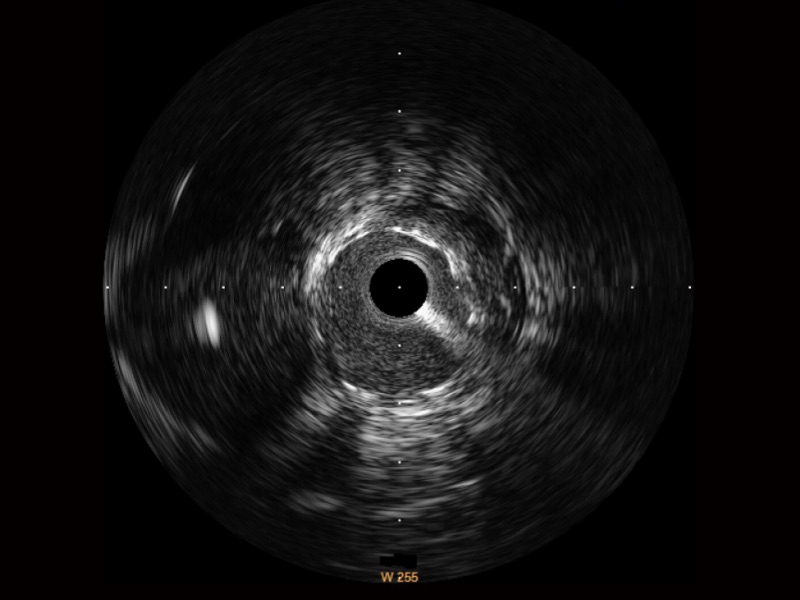

乐玩lewin国际宽频IVUS图像

对比传统IVUS导管成像,乐玩lewin国际宽频IVUS图像的近场支架梁显影更细腻,远场中膜外血管仍清晰可辨,兼顾远中近,兼顾分辨力与穿透深度